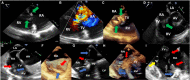

Compared with the extensive data on left-sided infective endocarditis (IE), there is much less published information on the features and management of right-sided IE. Right-sided IE accounts for 5% to 10% of all IE cases, and compared with left-sided IE, it is more often associated with intravenous drug use, intracardiac devices, and central venous catheters, all of which has become more prevalent over the past 20 years. In this manuscript on right-sided IE we provide an up-to-date overview on the epidemiology, etiology, microbiology, potential locations of infection in the right heart, diagnosis, imaging, common complications, management, and prognosis. We present updated information on the treatment of pacemaker and device infections, infected fibrin sheaths that appear to be an easily missed source of infection after central line as well as pacemaker removal. We review current data on the AngioVac percutaneous aspiration device, which can obviate the need for surgery in patients with infected pacemaker leads and fibrin sheaths. We also focused on advanced diagnostic modalities, such as positron emission tomography/computed tomography. All of these are supported by specific case examples with detailed echocardiographic imaging from our experience.